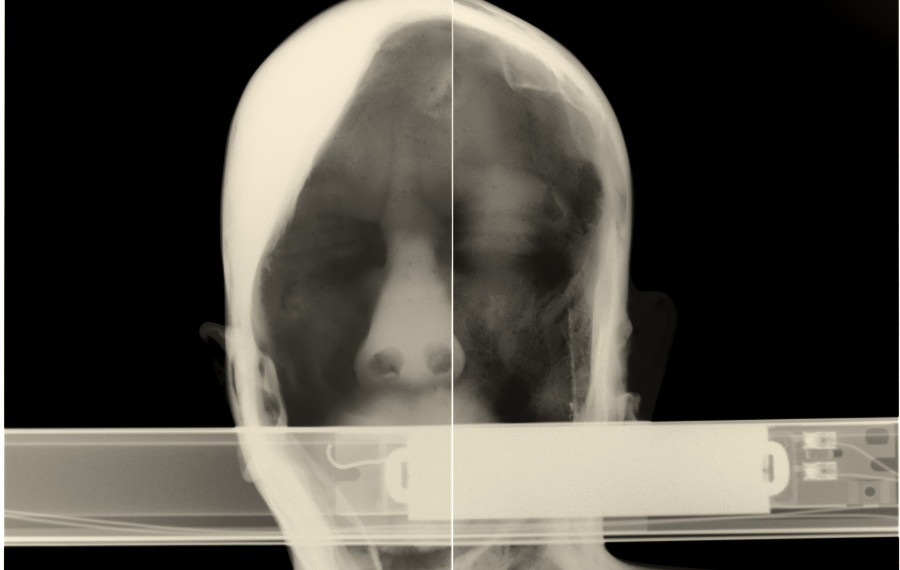

Artifacts of Evidence / Dokazno gradivo je prostorska instalacija umetniških del studia Paul O Robinson v dialogu s knjigo-artefaktom umetnice in oblikovalke Maje Licul. Preobraženim objektom in prostorom iz hiše Jožeta Plečnika so sopostavljena dela, ki izhajajo iz kontinuiranega raziskovanja interierjev in eksterierjev v Sloveniji in Italiji – v slednji natančneje v muzeju Fortuny v Benetkah. Postavitev se ukvarja z vprašanji stalnosti in minljivosti ter preoblikovanja konvencionalnih znakov v nove snovne oblike. Rentgenska dokumentacija je pretvorjena v slikarske in kiparske forme, pri čemer se skrita vsebina razgrinja v nove prostorske strukture.